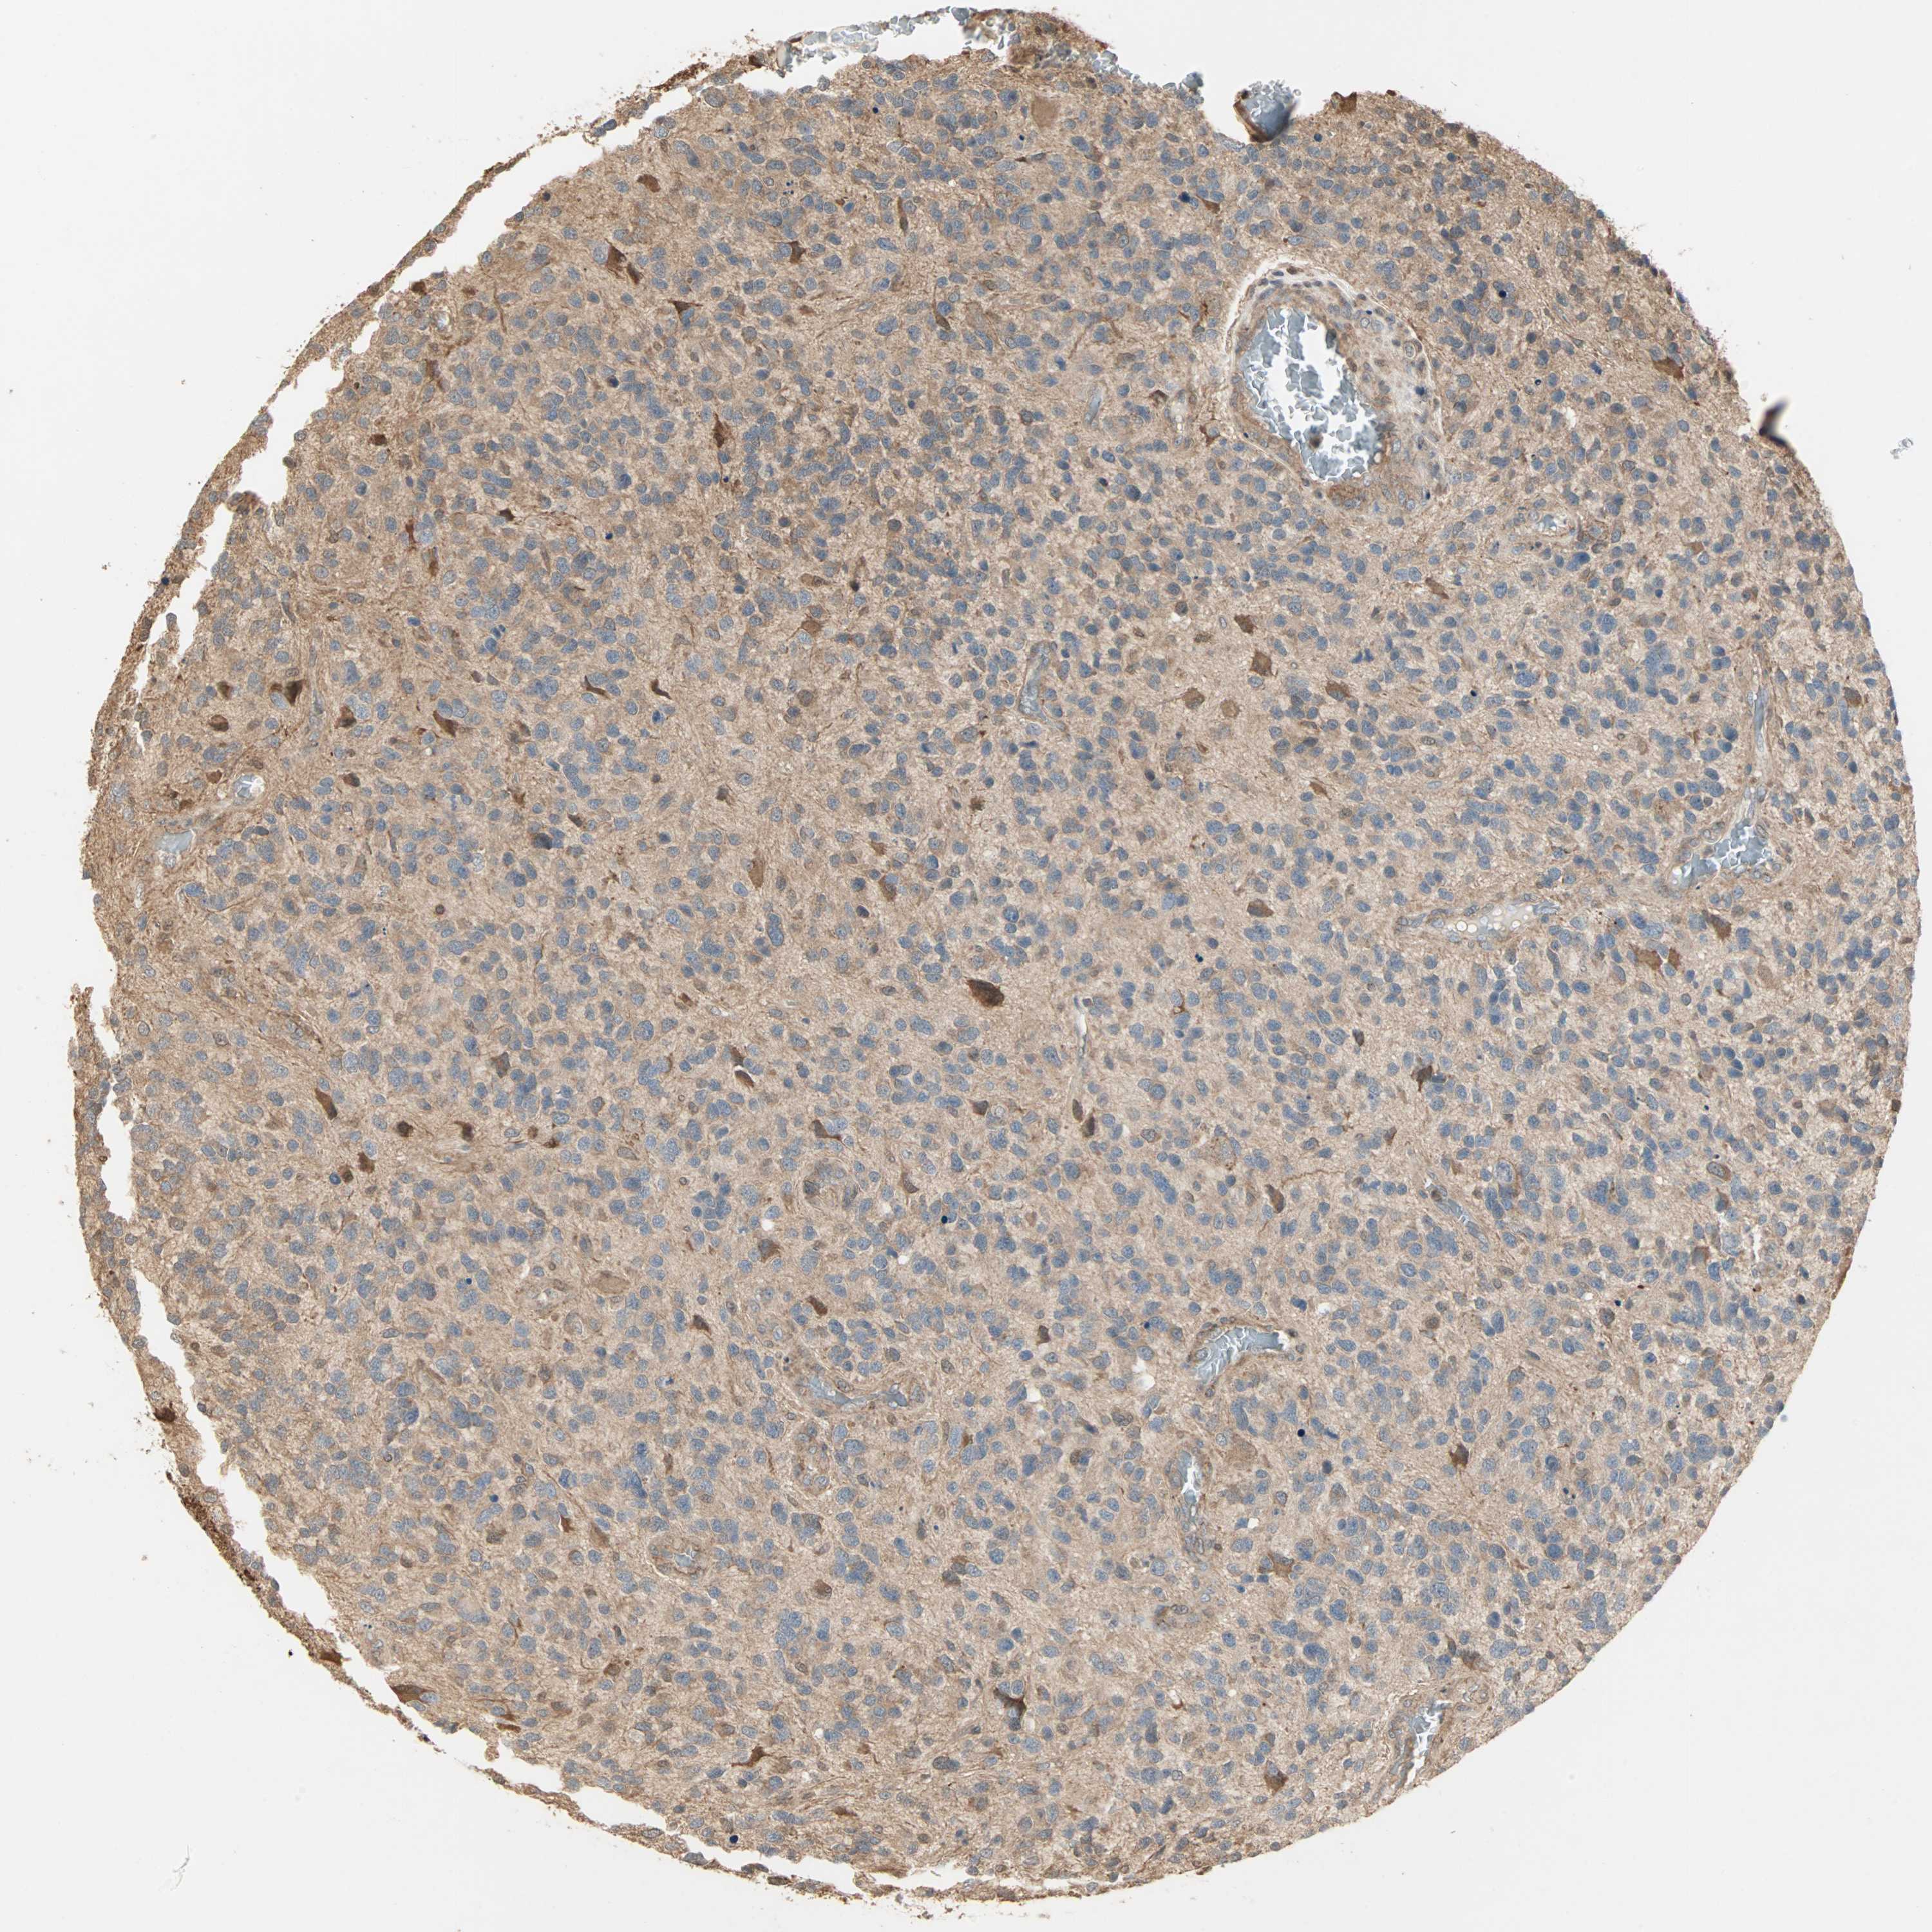

GLIOMA - Protein expressioni

A mouse-over function shows sample information and annotation data. Click on an image to view it in a full screen mode. Samples can be filtered based on level of antibody staining by selecting one or several of the following categories: high, medium, low and not detected. The assay and annotation is described here.

Note that samples used for immunohistochemistry by the Human Protein Atlas do not correspond to samples in the TCGA dataset.

Antibody stainingi

Antibody staining in the annotated cell types in the current human tissue is reported as not detected, low, medium, or high, based on conventional immunohistochemistry profiling in selected tissues. This score is based on the combination of the staining intensity and fraction of stained cells.

Each image is clickable and will lead to virtual microscopy that enables deeper exploration of all samples and also displays staining intensity scores, fraction scores and subcellular localization as well as patient and tissue information for each sample.

Antibody HPA007716

Staining

High

Medium

Low

Not detected

Intensity

Strong

Moderate

Weak

Negative

Quantity

>75%

75%-25%

<25%

None

Location

Nuclear

Cytoplasmic/membranous

Cytoplasmic/membranous,nuclear

Glioma, malignant, Low grade

Glioma, malignant, High grade